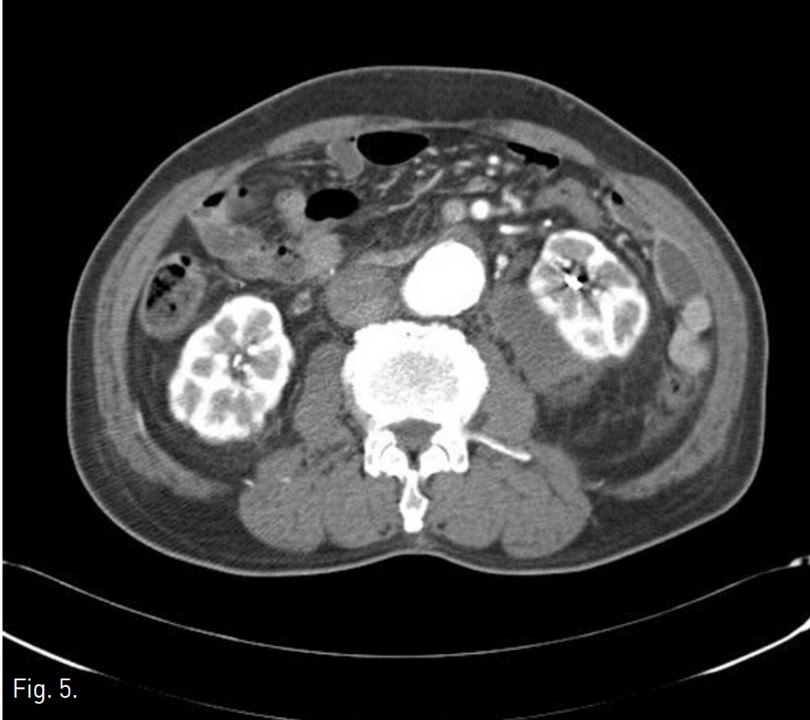

우측 총대퇴동맥을 천자하여, 5Fr sheath(Terumo, Tokyo, Japan)를 통해 5Fr Cobra catheter(Cook, Bloomington, USA)를 좌측 신동맥 기시부에 위치하여 혈관조영술을 시행하였다. 좌측 콩팥의 하극 부위 콩팥동맥 분지에서 조영제 누출이 있었다(Fig. 3). Microcatheter(Stride, Asahi Intecc co., Japan)로 출혈이 있는 신동맥 분지를 선택하여 microcoils (3x2mm, Tornado embolization microcoil, Cook, Bloominton, USA) 3개와 gelatin sponge particles (Gelfoam, Upjohn, Kalamazoo, MI, USA)을 이용하여 색전술을 시행하였다. 이후 시행한 혈관조영술에서 더 이상의 조영제 누출이 보이지 않아 시술을 종료하였다(Fig, 4). 이후 8개월 뒤 추적 전산화단층촬영에서 좌측 콩팥주위 혈종은 매우 크기가 감소하였다(Fig. 5).

Fig. 5.

Fig. 5. Follow up CT obtained after embolization of renal artery shows decreased size of left perirenal hematoma.